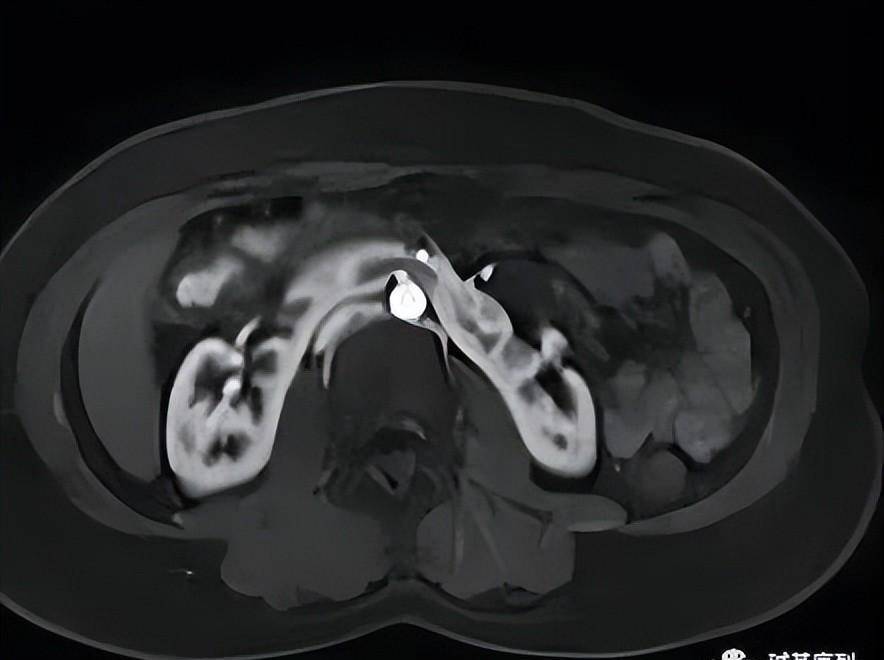

马蹄肾是最常见的融合肾,是两侧肾脏下极由实质性峡部或者纤维性峡部连接而成马蹄肾的峡部位于主动脉和下腔静脉前方13的马蹄肾合并其它畸形,发现马蹄肾要做全身检查,排除合并心血管胃肠道泌尿生殖系统畸形主要是做B超CT检查13的小孩子没有症状,不需要特别处理如果出现积水感染或。

拥有马蹄肾的个体可能伴随其他发育异常,如肾盂输尿管连接部的狭窄重复输尿管膀胱输尿管返流等生理变化融合的肾脏改变了原本的血管和排尿管道路径尿液从肾脏排出的位置升高,增加了尿液流动的阻力可能的并发症肾积水由于尿液流动阻力增加,可能导致肾积水结石肾积水长期存在可能形成结石。